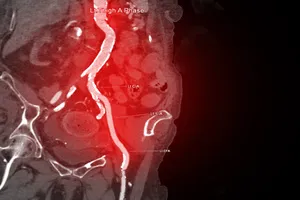

4. 담석증

담석이 담도를 막아 담즙의 흐름을 방해하면 담낭염이나 췌장염과 같은 합병증이 발생할 수 있습니다. 이 경우, 오른쪽 상복부에 심한 통증과 함께 소화불량, 황달 등의 증상이 나타날 수 있습니다. 약물 치료로 통증을 완화하고 염증을 가라앉힐 수 있으며, 필요에 따라 체외충격파쇄술이나 수술을 통해 담석을 제거할 수 있습니다.